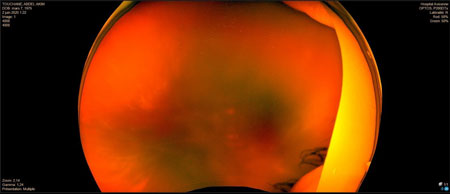

DR tractionnel préop

RDP_img7

DR tractionnel post op

RDP_img8